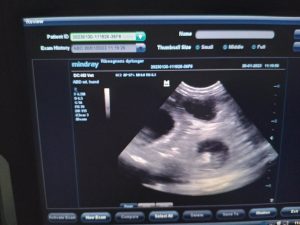

Olympia wurde am 30. januar gescannt mit ungefähr 7 welpen.